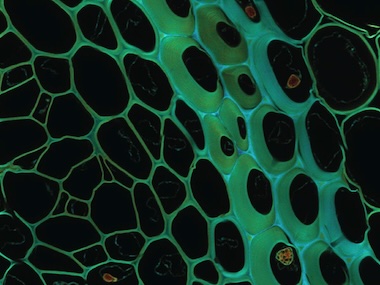

A project at the Italian Institute of Technology (IIT) has developed a method able to carry out simultaneous super-resolution imaging and optical sectioning in laser scanning microscopy.

Described in Nature Photonics, the technique allows scientists to see and photograph biological samples in all their complexity, said the team, obtaining clear and detailed images.

The team developed a method for taking single-plane image data and reconstructing super-resolution optical sectioning, naming the technique super-resolution sectioning image scanning microscopy (ISM), or s2ISM.

IIT designed an instrument in which a small array of sensors captures both the light at the point where it hits a tissue sample, and the way the light then spreads within that sample. Once this information is recorded, a reconstruction algorithm identifies the path of the light through the sample, as a way to produce sharper and better-sectioned images without losing signal quality.

"The optical microscope used is equipped with an array of SPAD (single-photon avalanche diode) detectors, capable of detecting the arrival of individual photons with very high spatial and temporal precision," said Alessandro Zunino from IIT.

Trials applying the s2ISM method to cell cultures and zebrafish embryos confirmed that it could outperform conventional image reconstruction techniques, and could be extended to any laser scanning microscopy technique.